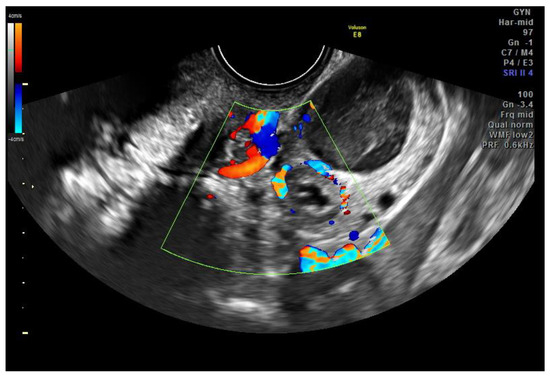

2.1. Case Report